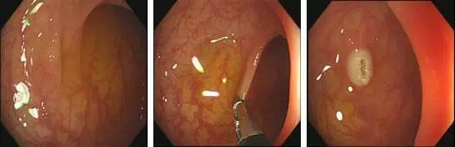

内镜下黏膜剥离术(EMR):

即在内镜下将病变黏膜剥离,并用高频电流完整切除。

热活检钳有什么作用【健康科普】发现胃肠息肉,到底要不要切?_https://www.jmylbn.com_新闻资讯_第5张

1.发现息肉2.于息肉基底部注射,抬起征阳性3.圈套器套扎息肉基底部

热活检钳有什么作用【健康科普】发现胃肠息肉,到底要不要切?_https://www.jmylbn.com_新闻资讯_第6张

1.息肉切除术后  2.钛夹夹闭创面